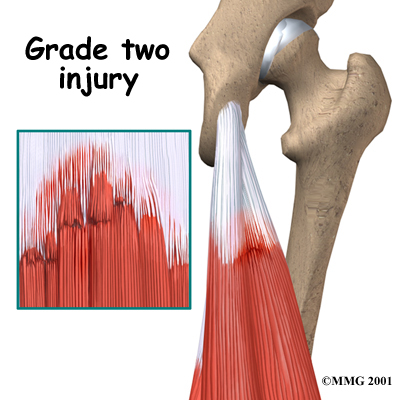

Hamstring injuries are grouped into three categories, according to the severity. The following images show each grade of injury:

Grade Two - Moderate

Grade one injuries are muscle pulls that do not result in much damage to the structure of the tissues. Grade two injuries are partial tears. Grade three injuries are complete tears.